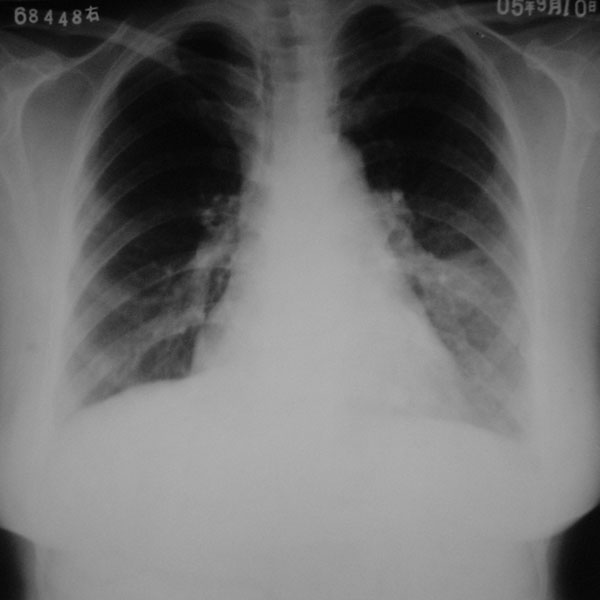

作者: hong630104 时间: 2006-2-21 15:21

标题: 回复:建议;站内肺部球型阴影讨论

再来个空洞性肺癌,男,58岁,有咳嗽,咳痰,咯血,我看到片子时已经是治疗后复查了,第一次片子,空洞里充满了积液。